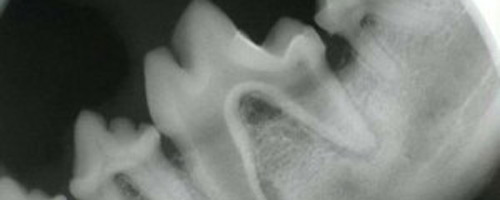

By the age of three, approximately 80% of dogs and 70% of cats have already developed periodontal disease. Left untreated, the infection can lead to tooth loss and bacteria from the mouth can spread through the bloodstream and cause kidney, liver, and heart problems. Oral disease is treatable regardless of the age of your pet and can be prevented by following a program of regular veterinary exams and a home dental care routine.

Dogs and cats both suffer from plaque and tartar build up which leads to gingivitis and periodontal disease. The periodontal disease is what causes tooth loss. We can prevent these from occurring in your pet with regular oral exams and cleanings as well as ongoing home care.